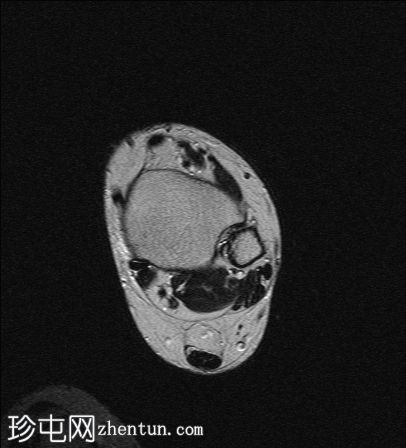

轴向

T2